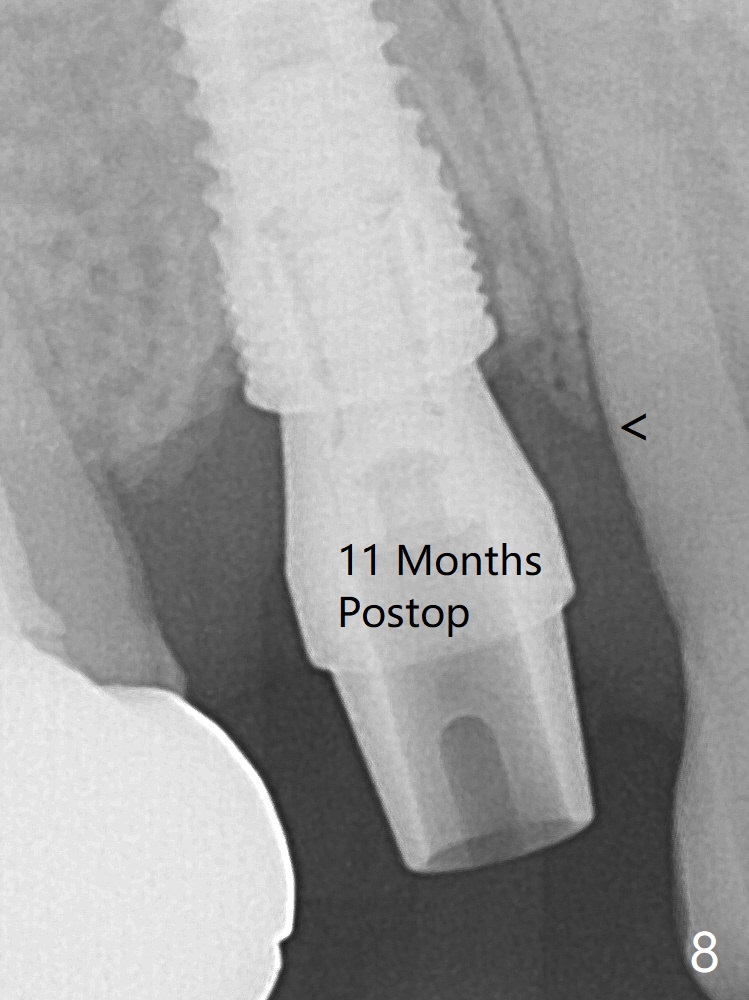

The buccal plate is normal at the tooth #5 (Fig.1) with the loose palatal fragment (Fig.2 P). Extraction leads to root fracture. Sectioning removes the palatal portion of the root and keeps the buccal semilunar piece (Fig.3 *); the mesiopalatal plate is resorbed (P). Initial osteotomy is off (Fig.4 (R: remaining root)). Redirection improves the trajectory (Fig.5). With the 2nd redirection (Fig.6 (4.5 mm tap)), a 4.5x12 mm implant is placed with 50 Ncm and sinus lift (Fig.7 black *); bone graft is placed with emphasis on the palatal defect (white *). As usual, an immediate provisional is fabricated. In fact the abutment may be not completely seated because of contact with the mesial crest. Prepare anesthetic and 5.5 mm profile drill. Take parallel BW or PA. Take occlusal photos to show no buccal or mesiopalatal atrophy. After 5.5 mm profile drill 11 months postop, the abutment has no contact with the mesial crest (Fig.8 <). Since the proximal contact between #3 and 4 is light with food impaction, the provisional at #5 is fabricated with tight distal contact. When the patient returns for final crown cementation (Fig.9), the food impaction is minimal between #3 and 4. The distal black triangle (Fig.10 *) and exposure of the abutment margin (^) are partially related to provisional fabrication and should dissolve over time considering socket shield.